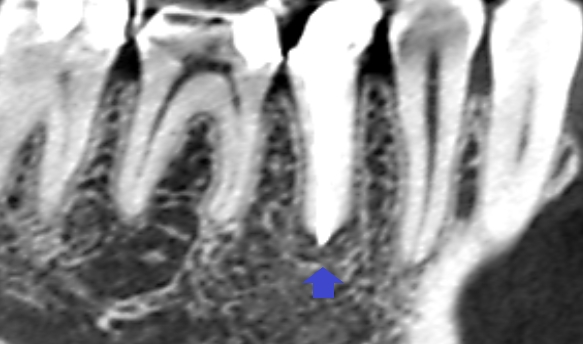

精密根管治療6ヶ月後の経過観察時のCT画像です。青い矢印の先にあった膿の影が消失し歯槽骨が再生しています。

根管治療をされている歯の根の先に膿がある場合は、細菌が歯根のどこかにいるということです。それを精査し、問題を解決することで膿が治ります。今回は、根管充填の不足が原因と考えられ、根の先までしっかり根管充填することで膿の改善が図れたケースでした。